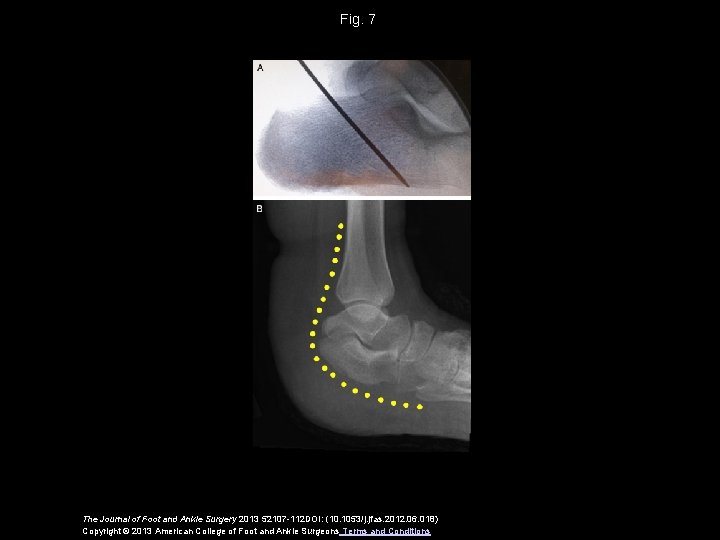

Fig. 7 The Journal of Foot and Ankle Surgery 2013 52107 -112 DOI: (10. 1053/j. jfas. 2012. 06. 018) Copyright © 2013 American College of Foot and Ankle Surgeons Terms and Conditions